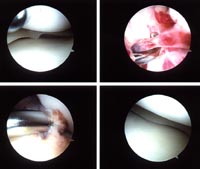

class. In June 1997 Dan had a partial ACL tear while executing a jump

ax kick (see pictures of orthroscopic surgury). The overstretched ACL

is shown in the upper right. He was getting close to the mirrors and

didn't want to hit them, so for some reason when he came down his

knee popped. He had surgery at the end of July 1997.